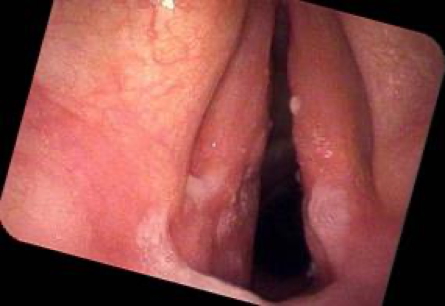

Acute

- Erythematous and oedematous true vocal cords

- Vascular injection

- Cord mobility typically remains normal